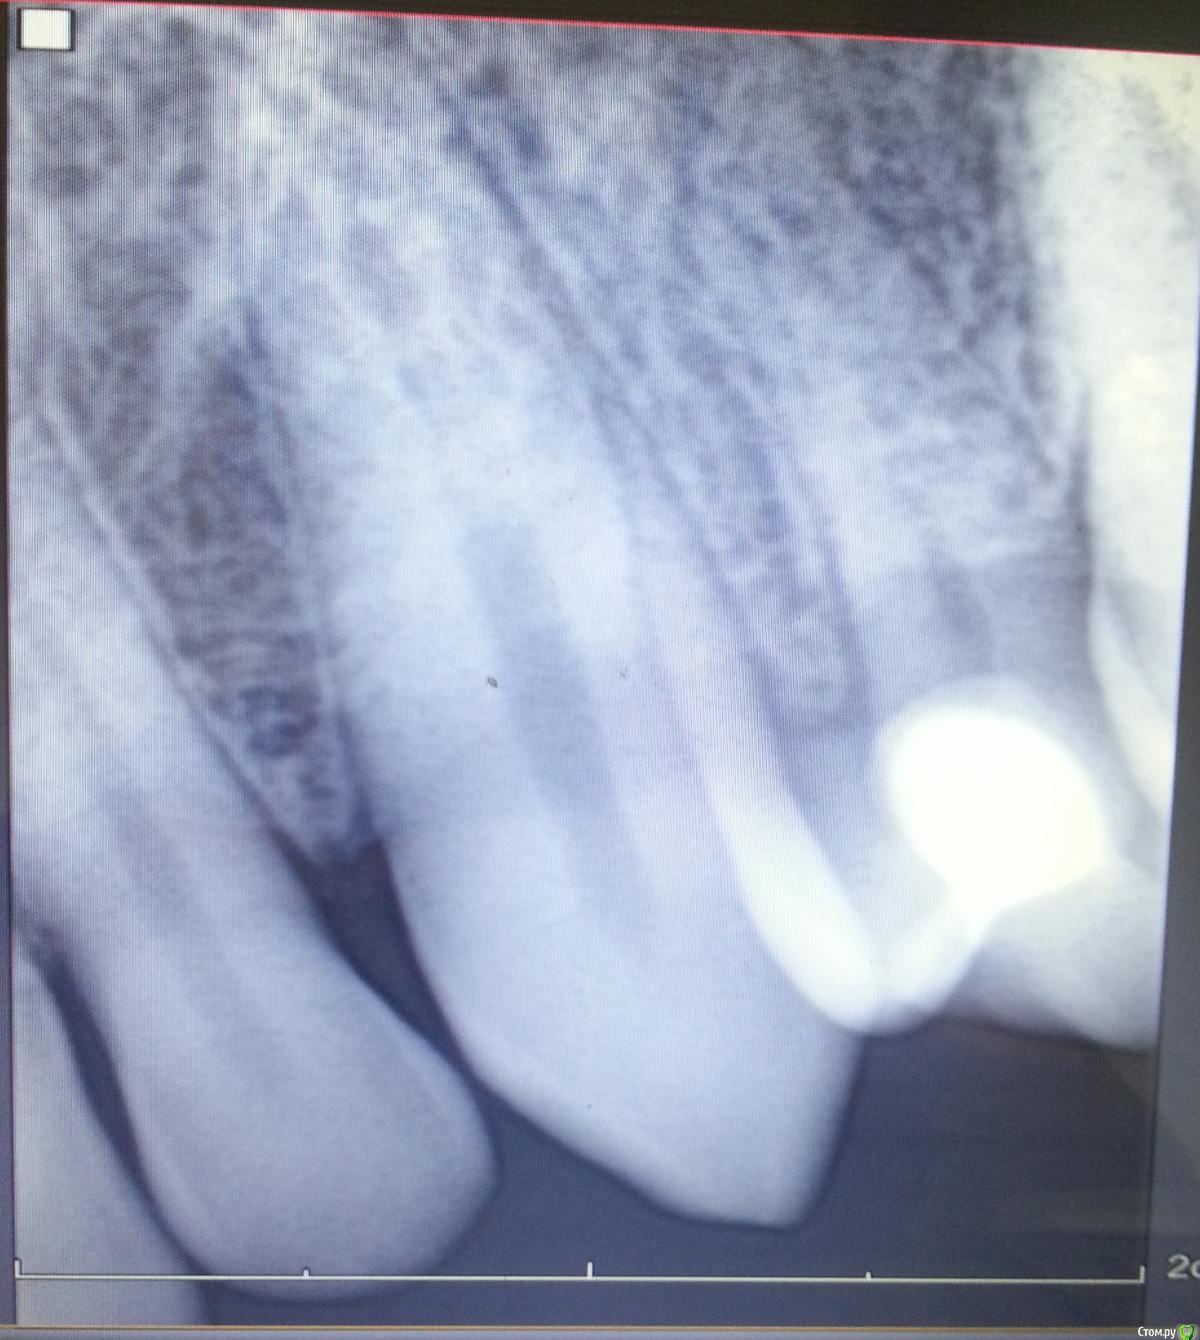

Nitrino1 Опубликовано 16 августа, 2015 Поделиться Опубликовано 16 августа, 2015 (изменено) Здравствуйте коллеги. Обратился пац. Субъективно: боли при давлении на этот зуб. Постоянных болей, спонтанных болей нет.Объективно: отсутствует 24й зуб (аномалия). После 23го сразу 25й. Небольшое покраснение маргинальной десны. Перкуссия 25го болезненна. Холодовой тест отрицательный. Судя по рг там должна быть пломба но внешне как то не определил. Плюс непонятное наложение на клык. Помогите разобраться. Есть мнение что это резорбированная 4ка. Изменено 16 августа, 2015 пользователем Nitrino1 Ссылка на комментарий

Nitrino1 Опубликовано 17 августа, 2015 Автор Поделиться Опубликовано 17 августа, 2015 (изменено) Вот Изменено 17 августа, 2015 пользователем Nitrino1 Ссылка на комментарий

Nitrino1 Опубликовано 23 августа, 2015 Автор Поделиться Опубликовано 23 августа, 2015 направляйте на кт!Панораму сделал пац в другой клинике, и там ему сказали "канал не заполнен до конца" )) Жду теперь снимок и его, если придет) Ссылка на комментарий